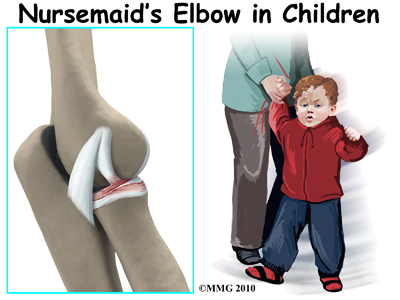

Nursemaid’s elbow is a common injury in young children. It occurs most often around age two and is rarely seen after age eight. Lifting the child up a step by the hand, giving the hand a sudden jerk, or pulling the child away from a dangerous situation can result in a subluxation or complete dislocation of one of the bones in the elbow. This condition is also known as pulled elbow or radial head dislocation.

In young children, the annular ligament of the radial head is thin and weak. A sudden pull on the forearm can tear this soft tissue structure. The radial head is pulled down through the tear. The annular ligament slips into the radiohumeral joint and becomes trapped between the two joint surfaces when the arm is let go. This is a radial head subluxation. When the annular ligament is pinched it causes pain.

This is a common injury in children. A sudden jerk on the arm is the main cause. As mentioned, lifting the child up a step by the hand, giving the hand a sudden jerk, or pulling the child by the hand or forearm away from a dangerous situation can result in an elbow injury of this type. Playing with other children where one child swings the other around by the arms can also result in this injury. The term ‘nursemaid’s elbow’ dates back to when nursemaids or nannies were the common caregivers who would be minding the children and most commonly holding onto their hands.